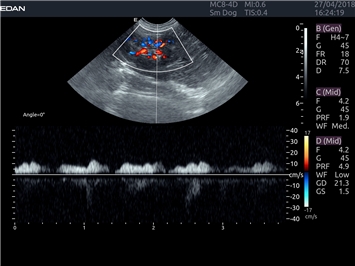

EDAN Acclarix LX4 VET представляет собой профессиональную ультразвуковую систему, специально разработанную для ветеринарных исследований. Сочетание стабильности, высокой производительности и эффективности делает эту систему идеальным выбором для современной ветеринарной практики.

Цветовой допплер:

Да

Импульсно-волновой допплер:

Триплексное сканирование: